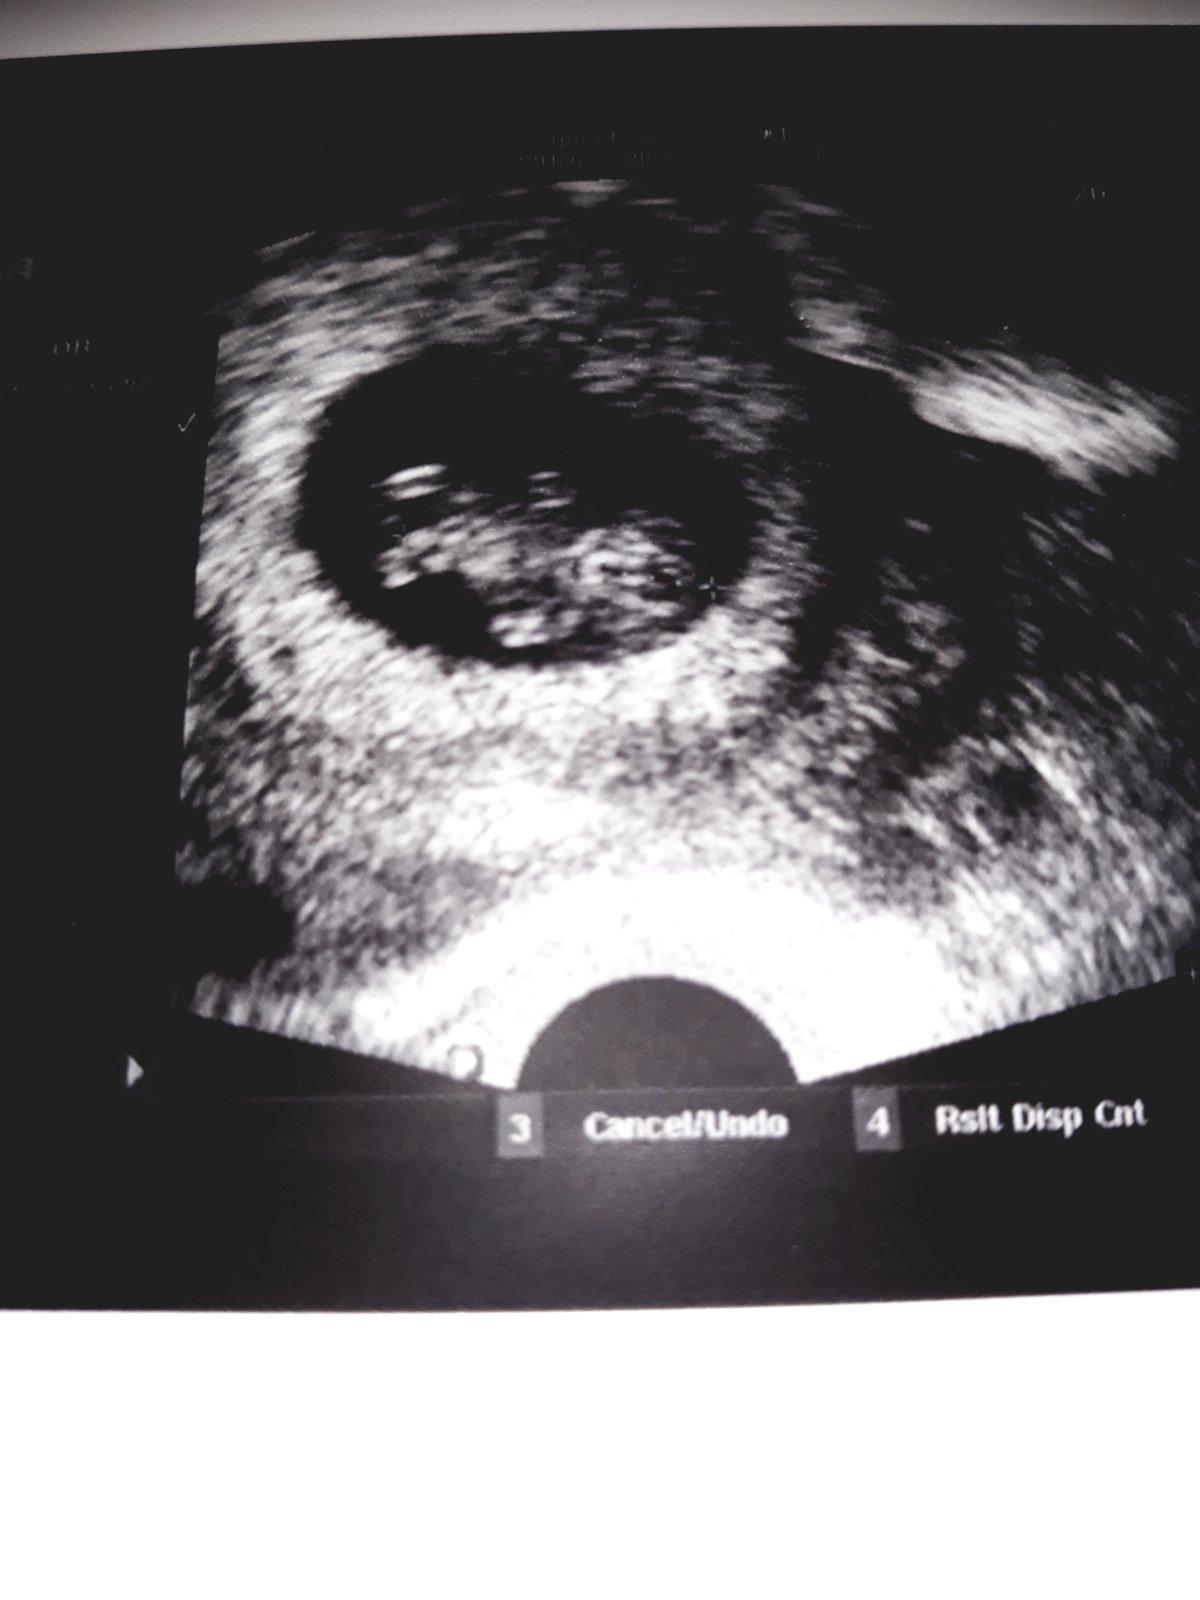

Ahoj holky, jen se hlásím, že zatím je vše v pořádku. Jen je mimísek menší, ale to se dalo čekat, a opravdu to souhlasí, že ovulka byla 22-23.12., takže podle toho to švagrová počítá a ani jsem si nemusela nic vymýšlet. Takže dnes končím 8.tt a už máme termín na screening v 1.trimestu. Na další poradnu jedeme 14.2., tak pak vložím zase fotečku.

@katmir Ahoj,SUPER!!!! Mám z Tebe velkou radost. To,že je miminko menší,nic si z toho nedělej, ze začátku prostě nešlo nic vidět,mělo pomalejší start. Ale věř tomu,že do 12.týdne vše dožene. Důležité je,že se vyvíjí a vše je jinak v pořádku. Držím palce,ať proplouváte týdny bez obtíží.